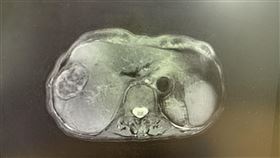

莫名骨痛纏身 當心癌症轉移至骨骼

1名75歲農夫,因經常在烈日與風雨下工作,早已習慣刻...

肝癌栓塞解不了,還能怎麼辦?一名80多歲肝癌婦人,接...